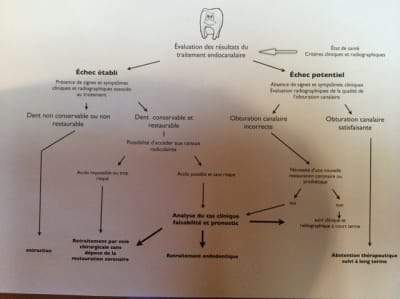

Pour ma part, je n'aurais pas entrepris de reprendre le traitement endodontique de la molaire. Si cliniquement, il n'y a aucun symptôme, je ferais la couronne dessus, point.

Y retourner comporte beaucoup de risques: préparation plus importante, stripping, fausse voie, fracture instrumentale et j'en passe.

Pour les deux incisives, évidement qu'il fallait reprendre.